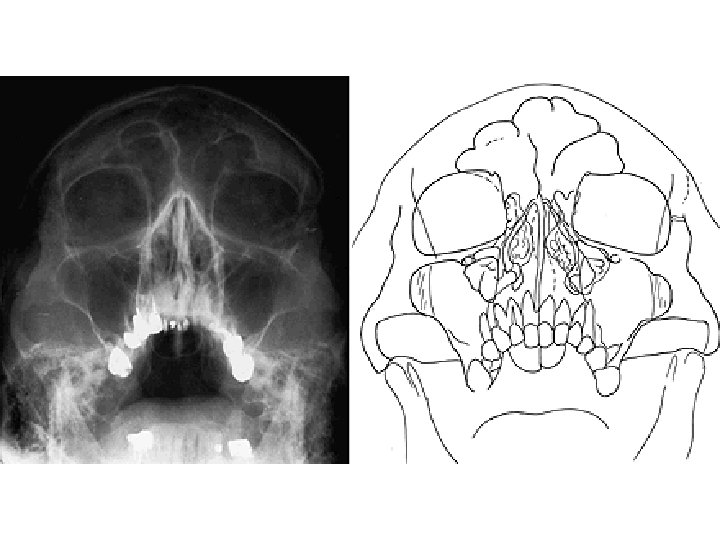

SINUS PARANASALES